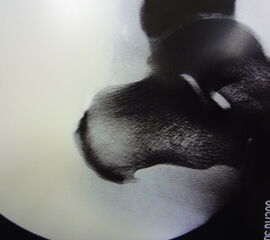

Abbildung 10, Video 5

Das OP-Ergebnis wird mit dem Bildwandler dokumentiert. Hierbei ist es wichtig, auch mediale und laterale Schrägaufnahmen anzufertigen, um keine weit posteromedial oder -lateral gelegenen Exostosenreste zu übersehen (Calcaneus seitlich, sowie 45° Innen- und Außenrotation). Ergänzend zu Röntgenaufnahme sollte der mediale und laterale Calcaneus abgetastet werden, um das Risiko einer belassenen Knochenkante möglichst gering zu halten. Der Hautverschluss erfolgt in Einzelknopftechnik, eine Ruhigstellung ist nicht erforderlich.